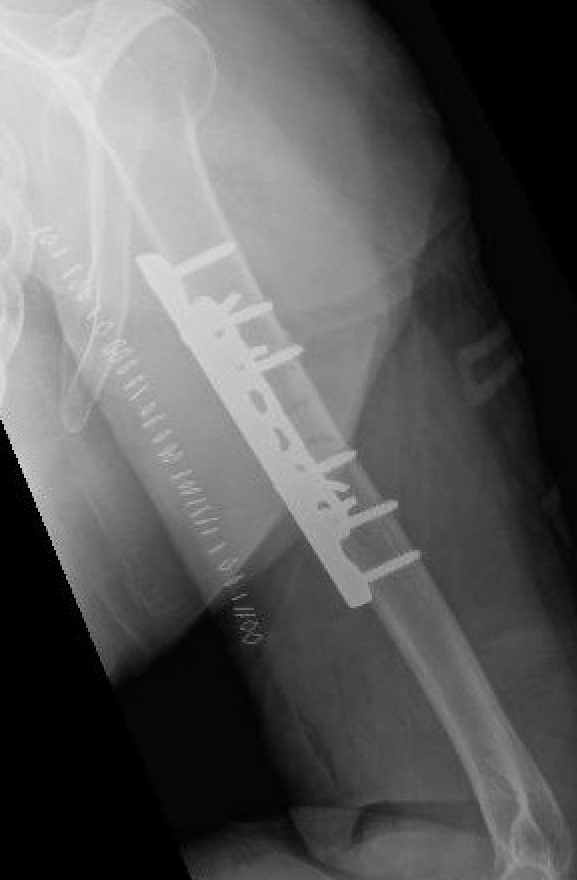

Technique

Approach

- fracture site dependent

- 4.5 mm plate with 6 cortices above and below

- if use 3.5 mm long proximal humeral plate, suggest 8 cortices below

- use iliac crest bone graft

- consider dual plating in proximal fractures with insufficient fixation, or in poor bone quality

Complications of ORIF

Nonunion

Revision of fixation to longer posterior plate